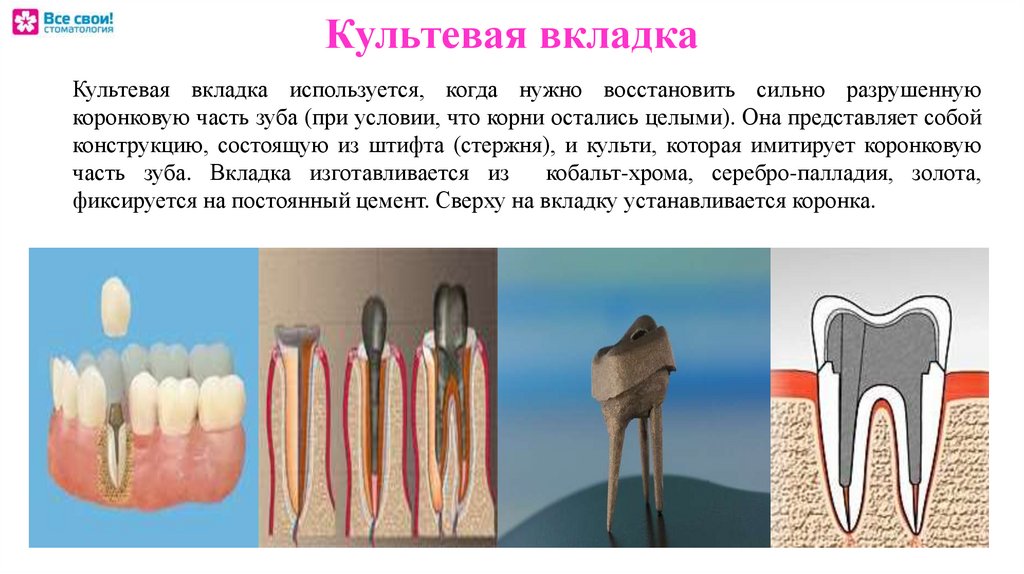

Культя зуба это

Культя зуба это 106 фото